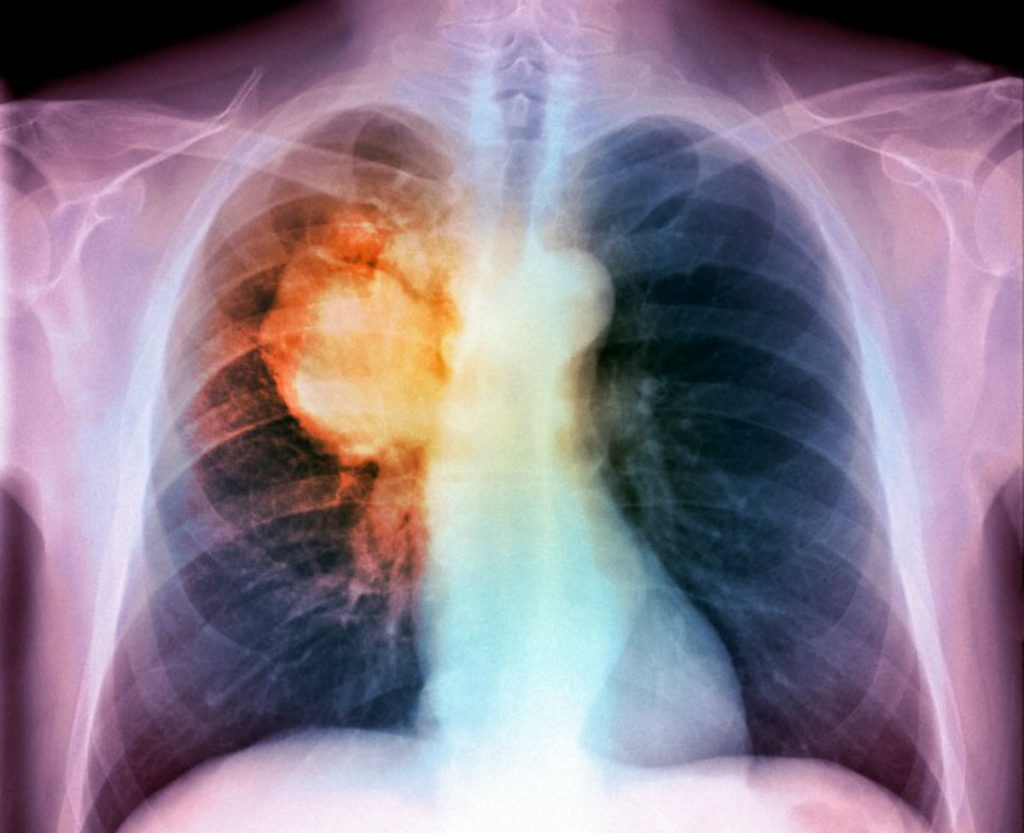

Tac spirale toracica a basso dosaggio di radiazioni (Ldct) e test microRNA sul sangue sono i due esami che, in combinazione, possono cambiare il destino di forti fumatori e soggetti ad alto rischio di sviluppo del carcinoma polmonare.

I miRNA sono piccolissime molecole, molto specifiche, che vengono rilasciate precocemente dall’organo aggredito dalla malattia e dal sistema immunitario.

I risultati sono stati significativi: il 58% dei partecipanti è risultato negativo a entrambi i controlli ed è stato classificato a rischio basso di tumore del polmone, mentre il 37% è risultato positivo a uno dei due esami (rischio medio) e il restante 5% ha avuto entrambi i valori positivi con un rischio molto più alto di ammalarsi.